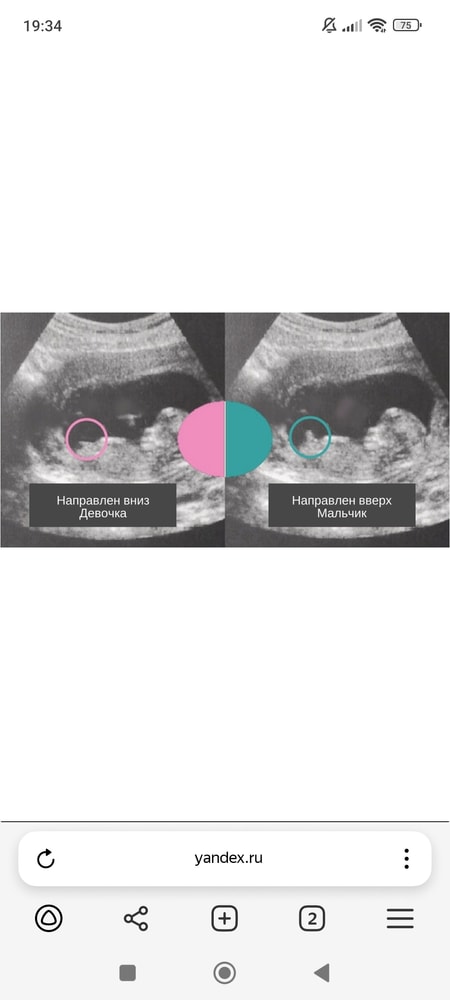

11 Нед , не могу понять, дев или мальчик 👦🧒

Вроде мальчик))

Еще рано. Даже опытный узист вам 💯 истину не скажет! Мне в 13 недель сказали, что мальчика жду, по факту после 20ой стало известно, что девочка будет 💖

На этом сроке еще не видно. Половой бугорок еще не отличается у них

Мне в 12 нед сказали,что девочка, так и ждём девочку)

Похоже на девочку, но это не точно 😁